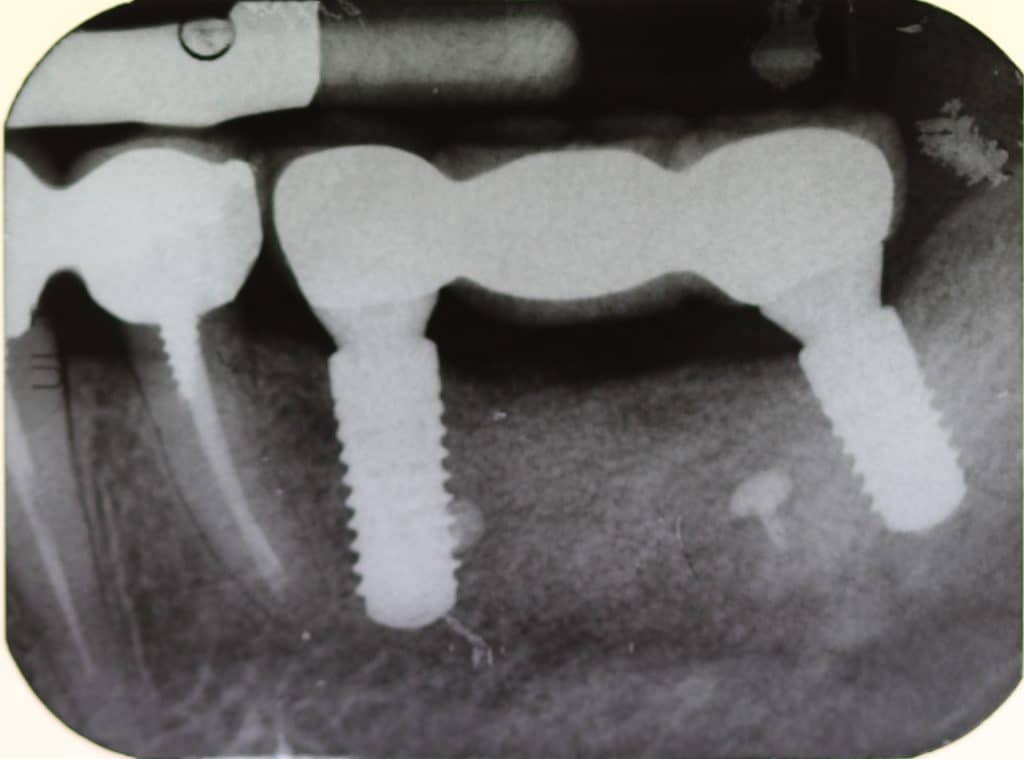

Initial radiographic situation

Radiographic evaluation after implant placement